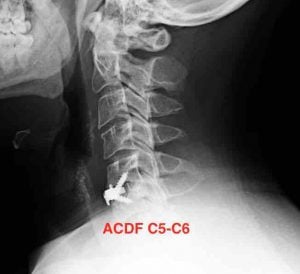

En el tratamiento quirúrgico de una hernia discal cervical la gran mayoría de especialistas optarán por una artrodesis cervical del segmento afectado, conocida por sus siglas ACDF (anterior cervical discectomy and fusión) que con una incisión por la parte anterolateral del cuello se accede hasta el disco afectado y se reemplaza por un espaciador que va a fusionar la vertebra superior e inferior.

RMN Columna Cervical: Cambios postquirúrgicos con material de fijación. Hernia discal C5-C6.

Hernia discal C5-C6, material de fijación C6-C7

Cirugía realizada en hospital HM Puerta del Sur en Móstoles. Controles radiológicos de la intervención quirúrgica.

RX Control Artrodesis Columna Cervical